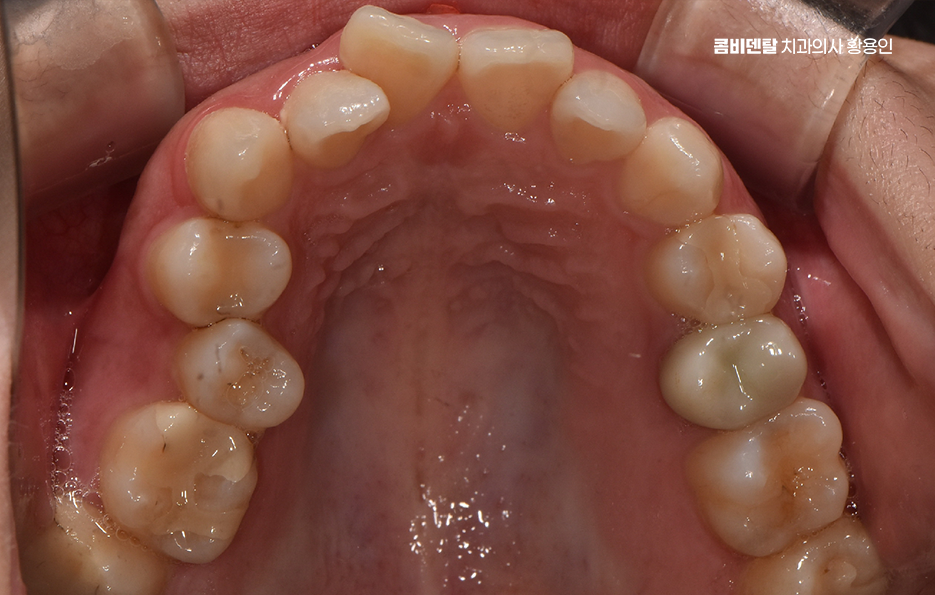

비발치 돌출입 교정 가능한 대표적인 케이스는 치아 배열의 공간이 비교적 충분한 경우로서 치아가 전체적으로 가지런하지는 않지만, 심하게 겹쳐 있지 않고 잇몸뼈 안에 어느 정도 여유 공간이 있는 경우에는 발치 없이도 치아를 뒤쪽으로 이동시키는 것이 가능한 경우가 있었어요.

치아 크기가 비교적 작거나, 턱의 크기에 비해 치아가 과도하게 크지 않은 경우도 비발치 돌출입 교정이 가능한 조건 중 하나로 같은 돌출입이라도 치아 크기와 턱뼈 크기의 비율에 따라 치료 접근이 달라지는데 치아가 상대적으로 작은 경우에는 공간을 확보하기가 더 수월하고 이런 경우에는 치아를 재배열하면서 자연스럽게 앞니 위치를 조정할 수 있었어요.

비발치 돌출입 교정에서 주로 사용되는 방법 중 하나는 악궁 확장으로 치아가 나 있는 폭을 넓혀서 공간을 확보한 뒤, 치아를 재배열하는 방식인데 이 방법은 공간을 만들어 발치 없이 교정을 진행할 수 있다는 장점이 있지만, 무리한 확장은 잇몸이나 치아 뿌리에 부담을 줄 수 있기 때문에 한계 범위 안에서만 적용되고 있어요

또 다른 비발치 방법은 어금니를 뒤쪽으로 이동시키는 방식으로 어금니를 뒤로 보내서 앞니가 들어갈 공간을 만드는 개념이며 치간 삭제 라는 방법도 있는데 치아 사이의 공간을 미세하게 조절하여 치아의 건강은 해치지 않으면서 치아의 이동 공간을 확보하는 방식이라 할 수 있었어요